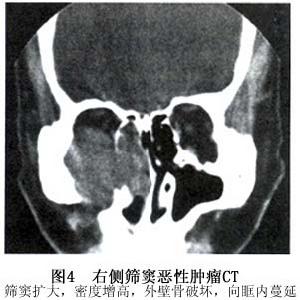

2.篩竇鱗狀細胞癌(squamous cell carcinoma of the ethmoidal sinus)篩竇鱗狀細胞癌不如上頜竇鱗狀細胞癌多見篩竇內腫瘤壓迫篩竇紙板樣的竇外側壁即眶內側壁引起篩骨紙板破壞腫瘤直接侵犯眼眶,腫瘤也可沿眶內側壁上的神經血管周圍的間隙進入眼眶,腫塊主要在眼眶內側引起眼球向外前移位發生復視。後組篩竇的鱗癌侵犯眶尖在眼球後眶尖處的腫塊除產生眼突外還可壓迫視神經、動眼神經和眼靜脈產生眼球運動障礙、凍結眼、上瞼下垂視力下降甚至失明眼瞼結膜水腫等類似於眶尖綜合徵的表現腫瘤侵及淚囊或鼻淚管,導致淚溢晚期,腫瘤除侵犯眼眶常轉移到頜下和頸上部淋巴結。

3.CT掃描 CT可明確揭示上頜竇癌眼眶侵犯,表現為上頜竇內中密度形狀不規則軟組織腫塊,眶下壁骨質破壞,並有軟組織腫物向眶內突出增強可見腫物明顯強化CT可發現70%~80%的病例有眶下壁的骨破壞,未見骨破壞者可能由於腫瘤通過神經周圍侵犯入眶。篩竇癌可見竇腔內中密度軟組織腫塊,眶內側壁破壞,眶內軟組織腫塊與篩竇相連眼球明顯受壓。